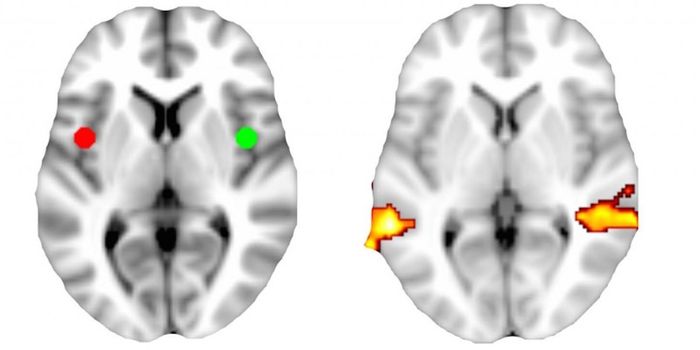

APR 27, 2021NeuroscienceResearchers from the University of Pennsylvania have found that people with schizophrenia may have a more permeable bloo ...